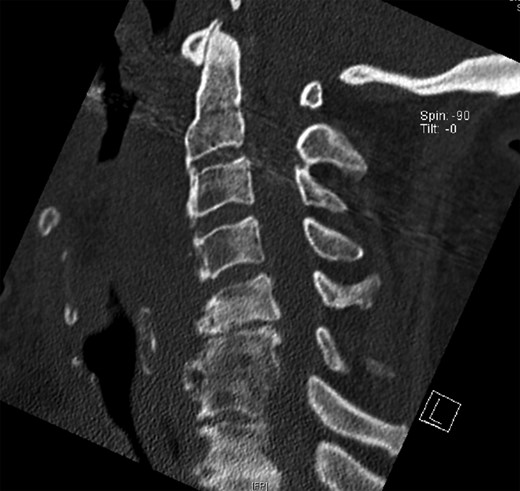

The X-ray and CT scan of the cervical spine revealed significant hyperostosis of the ventral cervical spine segments C3–C7. Hyperostosis was most extensive at segments C3–C5 causing stenosis of the pharyngeal lumen at the level of the larynx (Fig. 1). Due to accompanying joint pain, additional radiological examinations were performed. CT of the right shoulder showed extensive osseous proliferation of the medial humeral head reducing the articular space of the glenohumeral joint, as well as calcification of the rotator cuff (Fig. 2). In the left ankle, the CT scan revealed ossification of the deltoid ligament, and Kellgren grade 4 arthrosis of the tibiotalar and talocalcaneal joints (Fig. 3).

CT of the cervical spine in a sagittal view. Osteophytes of the ventral cervical spine segments C3–C5 protrude towards the oesophageal lumen.